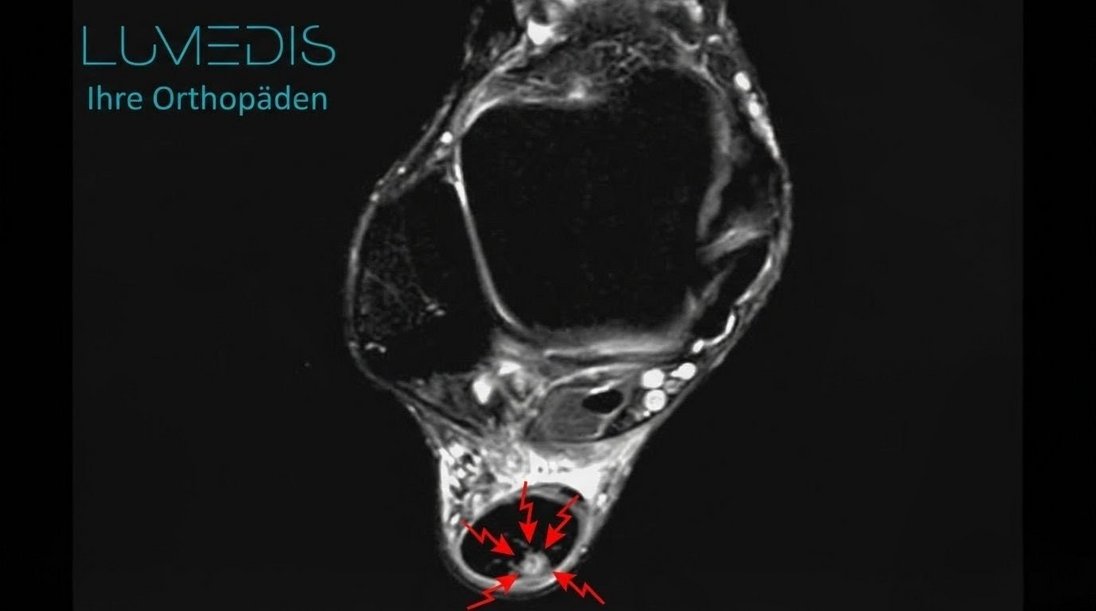

MRT einer angerissenen Achillessehne (Querschnitt)

MRT einer angerissenen Achillessehne im Querschnitt der Sehne (rote Pfeile zeigen auf den Anriss)